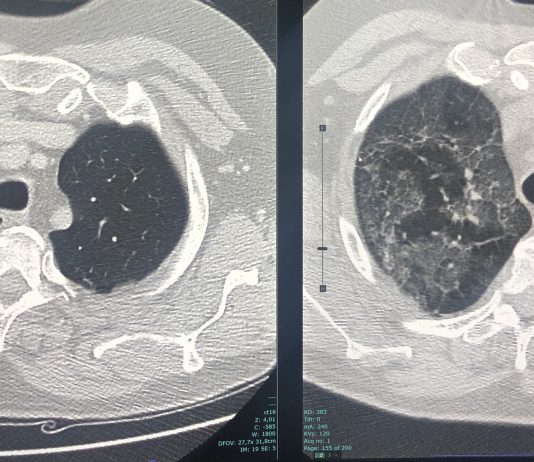

73-year-old male patient presented to the ED with fever for 10 days, not responding to paracetamol.